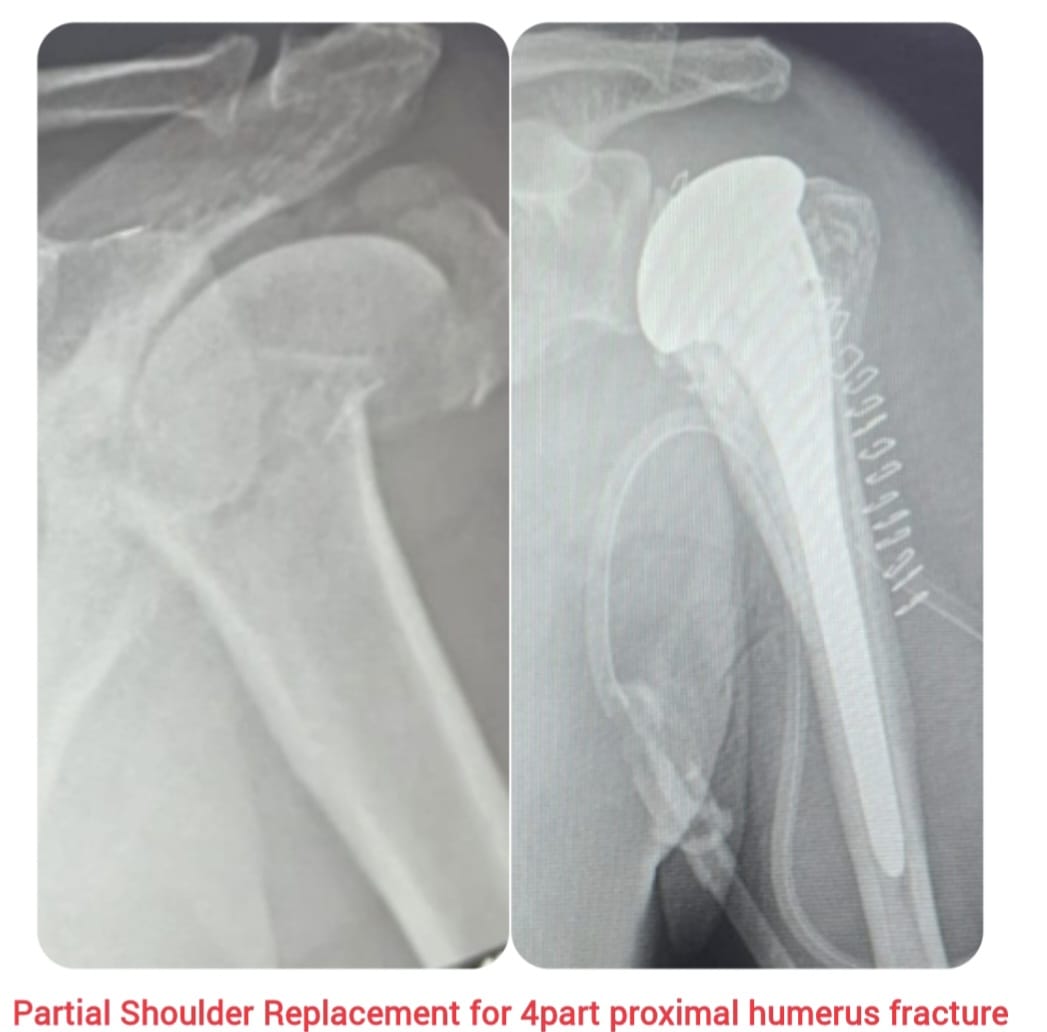

Partial shoulder replacement, also known as shoulder hemiarthroplasty, is a surgical procedure performed to relieve pain and restore function in patients with severe shoulder joint damage. In this procedure, only the damaged ball (humeral head) of the shoulder joint is replaced with a prosthetic implant, while the natural socket (glenoid) is preserved.

This procedure is commonly recommended for patients with specific conditions such as fractures of the humeral head, early-stage arthritis, or when the socket remains healthy. Advanced surgical techniques ensure better implant positioning, reduced tissue damage, and faster recovery with improved shoulder mobility and strength.